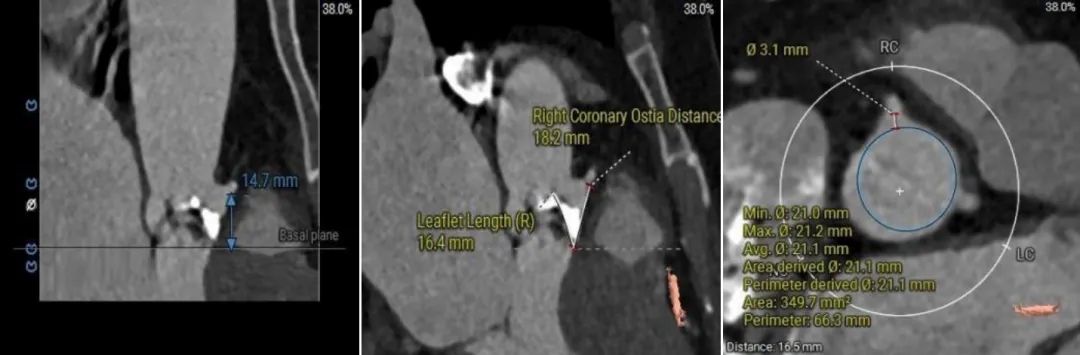

(1)Type 0二叶式主动脉瓣,瓣环适中,中度钙化,Type 0二叶瓣受瓣口形态及钙化影响,瓣架呈非理想椭圆形展开,对瓣架支撑力与顺应性提出了更高要求,同时该病例合并升主扩张,对同轴性和释放的稳定性提出了更高的要求。因此优先选择支撑性和顺应性兼具的瓣膜,以及较柔软花冠的瓣膜,降低对升主动脉的损伤,小锥角的设计进一步提升了瓣膜在释放的稳定性

(2)窦部空间较小,左侧瓣叶冗长,且开口位置在短轴平面,左冠冠脉风险较高,优先选择有收腰设计的瓣膜,降低冠脉风险并保留术后足够的VTC

综合病例解剖特点及患者年纪,决定使用第二代可回收的自膨瓣,可回收提高容错空间,为了降低冠脉阻挡风险,决定采用平衡收腰设计的TaurusElite 的瓣膜,先使用大鞘鞘芯进行预扩,然后上20F大鞘。